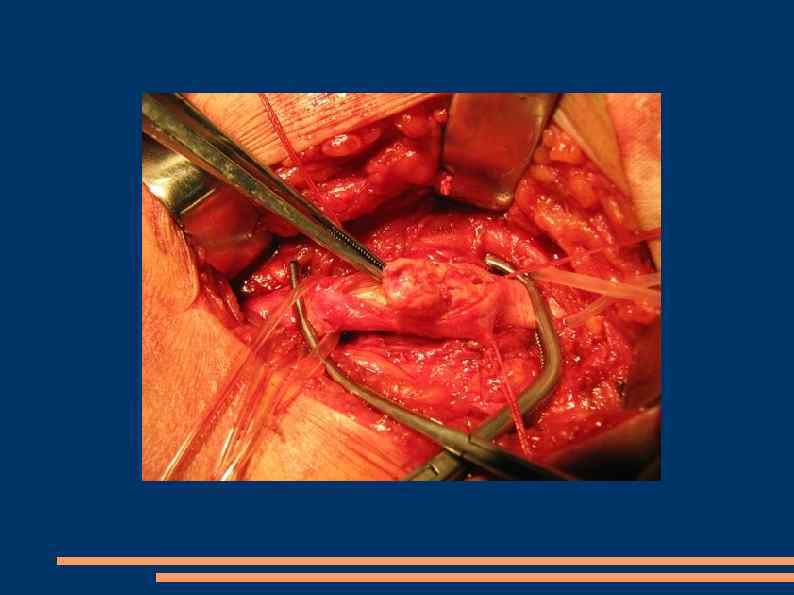

Эндартерэктомия Полуоткрытый способ Закрытый Открытый эверсионный

Открытая эндартерэтомия

Полузакрытая эндартерэктомия

Эверсионная эндартерэктомия